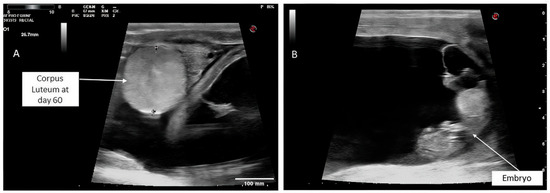

Administration of Human Chorionic Gonadotropin Combined with Phenylbutazone at the Time of Embryo Transfer Synergistically Improves Pregnancy Rates in Dromedary Camels

Effective luteal support is crucial for successful pregnancy following embryo transfer in dromedary camels, highlighting the importance of maintaining adequate luteal function. This study compared three luteal support protocols for pregnancy rates after embryo transfer (ET) in dromedary camels. Recipients with a single [...] Read more.

Effective luteal support is crucial for successful pregnancy following embryo transfer in dromedary camels, highlighting the importance of maintaining adequate luteal function. This study compared three luteal support protocols for pregnancy rates after embryo transfer (ET) in dromedary camels. Recipients with a single ovarian follicle (14~16 mm) were assigned into: (1) untreated control, (2) Phenylbutazone (PBZ) at 3.7 mg/kg IV prior to ET, or (3) human chorionic gonadotropin (hCG) 2000 IU plus 3.7 mg/kg IV PBZ prior to ET. Recipients that showed ovarian inactivity were treated with an injection of 1800 IU of equine chorionic gonadotropin (eCG) after progesterone (P4) priming. Pregnancy was assessed on days 10 (P4 assay) and 60 (transrectal ultrasonography) post-ET. Pregnancy rates on day 10 were higher in the hCG + PBZ (73.3%) and eCG (68.0%) groups than in the PBZ (44.0%) and control (35.0%) groups (p < 0.05). By day 60, the hCG + PBZ group exhibited the highest pregnancy maintenance rate (81.8%) and the lowest embryonic loss rate (18.2%), compared with eCG (53.0%; 47.0%), PBZ (54.5%; 45.5%), and control (57.1%; 42.9%) groups, respectively (p < 0.05). However, there was no significant difference among the eCG, PBZ, and control groups in embryonic loss rates. In conclusion, hCG synergizes with PBZ to enhance corpus luteum function, uterine receptivity, and pregnancy maintenance more effectively than PBZ or eCG. Full article